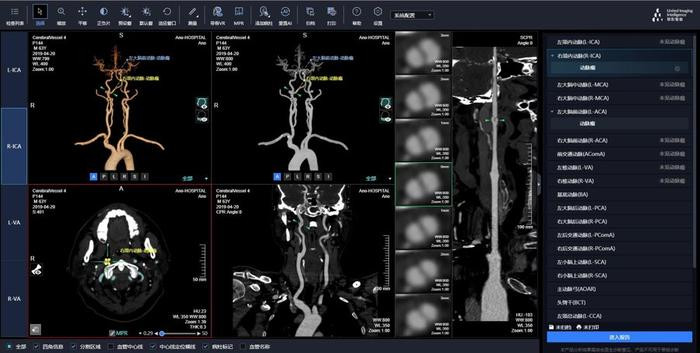

本年上市的三类医疗器械中,联影智能、微创集团研发的居品引东谈主着重,体现了上海两家头部企业的翻新实力。颅内动脉瘤CT血管造影图像援助检测软件是一款“东谈主工智能+医疗”居品,基于深度学习算法,能自动完成图像重建和颅内动脉瘤检测。它将图像重建时候裁汰了90%,为患者争取到贵重的抢救时候,同期能批驳轻细动脉瘤的漏诊率。这款联影智能开发的软件还买通了会诊历程中的图像存档、胶片打印、文书撰写等步伐,大幅提高医师的责任效能。刻下,动脉瘤AI援助会诊软件已在寰宇1800余家病院落地利用。

颅内动脉瘤CT血管造影图像援助检测软件的界面